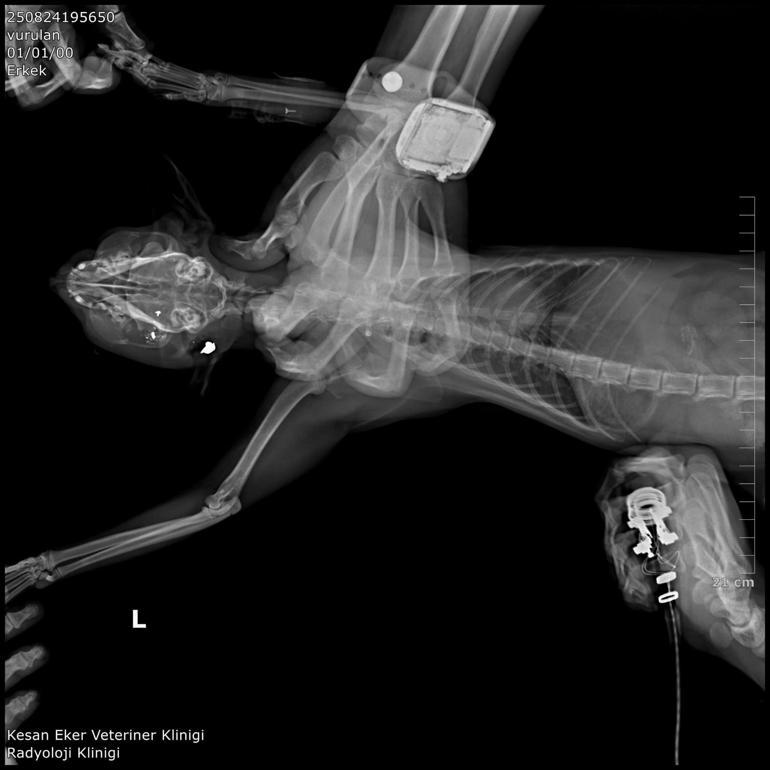

Hüseyin Bülbül ayrıca ölü bulunan kedileri özel bir kliniğe götürdü. Klinik raporunda, 'ateşli silah yaralanması ile uyumlu patolojiler' tespit edildiği, hayvanların tüfek saçması sonucu öldüğüne ilişkin bulgulara yer verildi. Bülbül, güvenlik kamerası görüntülerinden komşusu K.G.'den şüphelendi. Görüntülerde; K.G.'nin bahçesine giren bazı kedilerin aniden kaçtığını fark etti.

İpsala Cumhuriyet Başsavcılığı'nın olaya ilişkin hazırladığı iddianamede K.G., hakkında, 'Bir ev hayvanını veya evcil hayvanı kasten öldürme' suçundan 6 aydan 3 yıla kadar hapis cezası istendi. İddianamede, "Herhangi bir silah ateşleme görüntüsü tespit edilmese de şüphelinin ikamet ettiği evin bahçe kapısı önünde bir kedinin can çekiştiği ve bir kedinin de kaçtığının tespit edildiği, dosya kapsamında tanık olarak beyanı alınan S.Ç.'nin şüphelinin bahçe kapısı önünde bir kediyi yatar vaziyette gördüğünü, başını sevmek istediğinde kedinin ölü olduğunu fark ettiğini, kediyi eline aldığında başından kan aktığını görmesi üzerine yol üzerinde kalmaması amacıyla kediyi çöp tenekesinin içerisine bıraktığını, ölen ve yaralanan 2 kedi hakkında düzenlenen 25/08/2025 tarihli veteriner hekim ön muayene raporu ile çekilen radyografilerde ateşli silah yaralanması (kuş saçması) ile uyumlu patolojiler gözlemlendiği şeklinde rapor tanzim edildi. Tüm dosya kapsamı incelenmekle şüpheli savunması, bilgi sahibi beyanları, İpsala İlçe Tarım Müdürlüğü'nün yazılı başvurusu, müşteki beyanı, kamera görüntüleri ve kriminal raporları birlikte değerlendirildiğinde, şüphelinin olay tarihinde müşteki Hüseyin Bülbül tarafından da beslenmekte olan sokak kedilerine ateş etmek suretiyle, bir kedinin ölümüne neden olarak üzerine atılı suçu işlediğine dair ve bir kedinin yaralanmasına neden olarak tariflenen suçu işlediğine dair hakkında kamu davası açmak üzere yeterli şüphe oluşturacak kadar delilin mevcut olduğu anlaşılmakla" denildi.

Hüseyin Bülbül'ün avukatı Edirne Barosu Keşan Temsilcisi ve Hayvan Hakları Komisyonu Başkanı Büşra Ağır Ürkmez, kedilerin 2018 yılından bu yana sistematik olarak öldürüldüğünü belirterek, "En somut adımlar, 24 Ağustos 2025 tarihiyle Hüseyin Bülbül'ün şikayet etmesi neticesinde başlamıştır. Davanın ilk celsesi görüldü. İlk celsede deliller toplandı. Balistik rapor sonucu dosyaya ibraz edilmiştir. Şüpheli beyanlarında suçu işlemediğini, bu olayla ilgi ve alakasının olmadığını söylemişse de dosyadaki mevcut deliller, tanık beyanları şüphelinin ifadelerinin gerçeği yansıtmadığını ortaya çıkarmaktadır. Bu konuyla ilgili olarak davanın takipçisi olacağız" dedi.

K.G.'nin kedileri bahçesinde ateşli silah ile vurduğunu belirten Ürkmez, "Bununla ilgili delillerimizi dosyayla sunmuş bulunmaktayız. Onun haricinde veteriner ön raporunda da kedilerin ölümüyle ilgili olarak vücutlarında saçma bulunduğu açıklığa kavuşmuştur. Kamera kayıtlarımızı da delil olarak dosyayla sunduk. Bu konunun takipçisiyiz. '5199 sayılı Hayvan Haklarını Koruma Kanunu gereği de şüphelinin ceza alması için elimizden gelen her şeyi baro olarak yapmak niyetindeyiz. Bununla ilgili son kararı mahkeme verecektir. Şüphelinin yurt dışına çıkış yasağı ve adli kontrolü ise devam etmektedir" diye konuştu. Hüseyin Bülbül ise davanın sonuna kadar takipçisi olacaklarını kaydederek, K.G.'nin hak ettiği cezayı almasını istediklerini söyledi. (DHA)